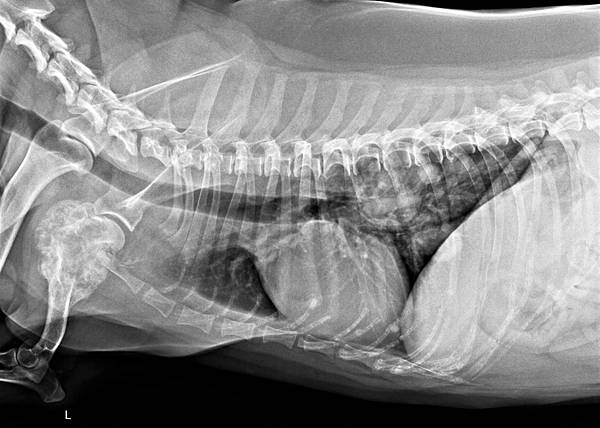

貓的肺部腫瘤

- Sep 15 Sun 2019 04:11